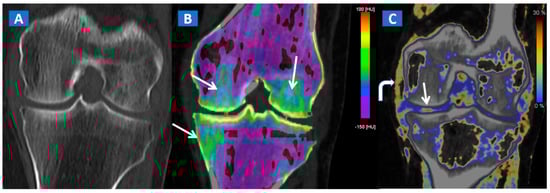

DECT can also accurately depict BME in post-traumatic fractures of the knee (Figure 5). Specifically, DECT can identify BME associated with ligamentous injuries following indirect trauma [6,15]. Moreover, additional color-coding can be used to better delineate meniscal tears (Figure 6). OCL, of the knee or ankle, are usually apparent from a markedly oedematous subchondral region (such as femoral condyle or astragalic dome), surrounded by a more subtle BME (Figure 7). With the availability of isotropic high-resolution CT images, it is possible to rule out migrated fragments and to confirm the integrity of the cortical bone.

A 65-year-old female with a post-traumatic medial menisci rupture and diffuse BME. On the standard 1 mm reconstructed coronal CT image (A), there are no signs of fracture. On the corresponding 2D 1 mm reconstructed 2D DECT image (B), the BME appears more pronounced on the femoral condyles and on the medial tibial plateau (arrows). By using different color-coding (C), it was possible to identify a rupture of the medial menisci (straight arrow), with thickening and oedema of the medial collateral ligaments (curved arrow).